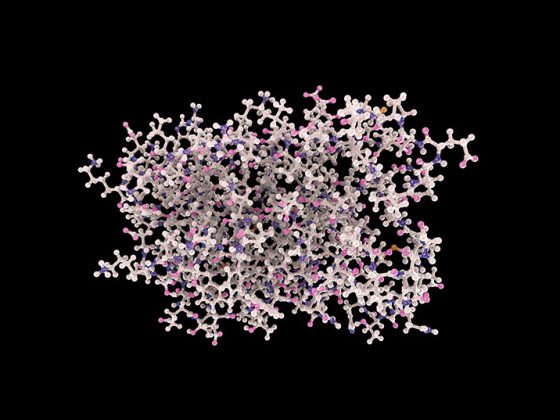

Eine Lokaltherapie mit topisch applizierten Retinoiden ist eine bewährte Behandlungsstrategie bei Aknepatienten. Beim neusten Vertreter dieser Medikamentengruppe handelt es sich um ein Trifaroten. Das Präparat ist für die äusserliche Behandlung der mittelschweren Akne vulgaris im Gesicht und am Rumpf indiziert und hat in klinischen Studien vielversprechende Ergebnisse gezeigt.